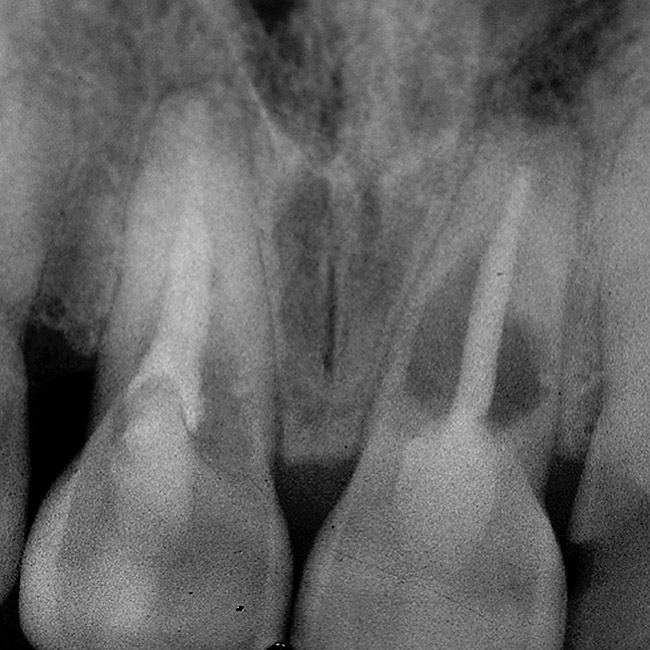

Figure 20  Soft-tissue levels were acceptable, but significant bone loss was present.

Figure 20

Teeth Are Present and Need Removal and Have Periodontal Disease

If the above scenarios present and the teeth have pre-existing bone loss, new challenges exist. Specifically, the papilla height in the areas of the periodontal disease becomes less predictable after tooth removal. This often leads to a greater degree of papillary recession and a more apically placed contact in the restorations to avoid an open gingival embrasure. In these situations, the clinician is faced with using implant restorations that will be functionally and structurally acceptable, but esthetically more difficult; or employing soft-tissue grafting and fixed partial dentures where the ability of grafting and the use of pontics can produce significantly more soft tissue over the interproximal bone (ie, 3.5 mm between adjacent implants vs 6.5 mm above bone for pontics). As a rule, the decision is based on the patient’s esthetic needs (ie, high lip line) vs the teeth’s condition. If the adjacent teeth are unrestored, it might remain preferable to use implants rather than prepare the unrestored teeth and live with esthetic compromise.